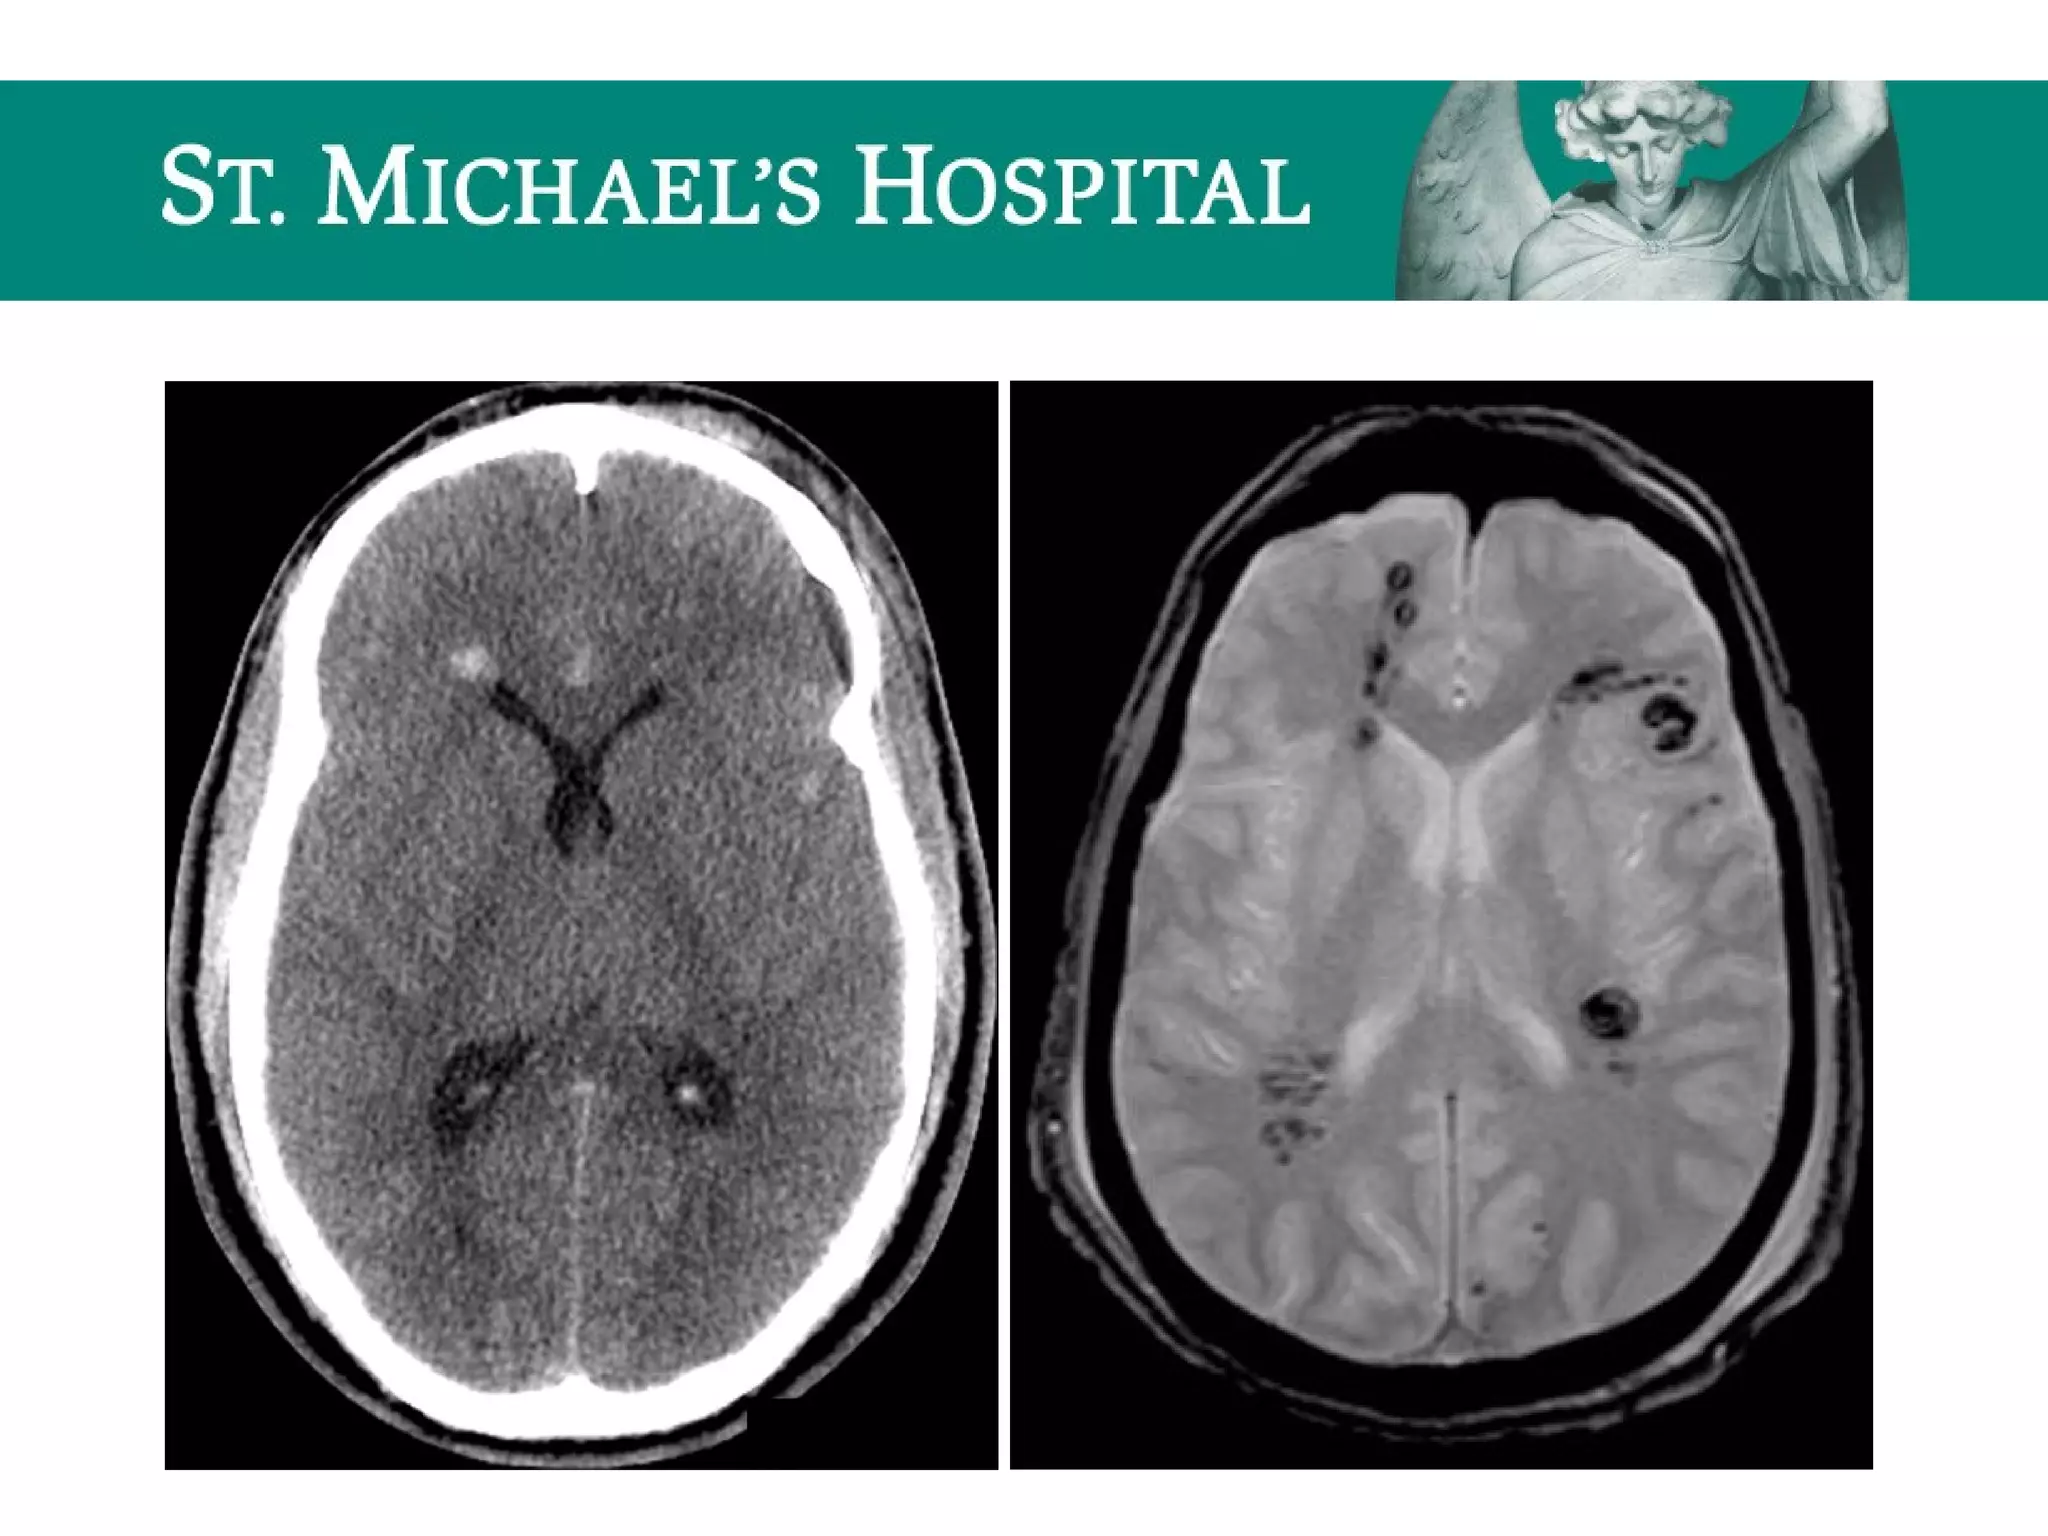

Diffuse Axonal Injury (DAI)

 Shear injury – secondary to severe rotational acceleration and

deceleration forces on the brain

 Unenhanced CT:

 Often normal (50-80%)

 Small hypodense foci due to traumatic edema

 Hyperdense petechial hemorrhages at the corticomedullary junction (20-50%)

 10-20% evolve to focal mass lesion (hemorrhage/edema)

 New lesions may become apparent on delayed scans

 Note: T2 GRE MR sequences are the most sensitive and demonstrate

hypointense foci at characteristic locations; microbleeds may only be

visible on GRE.

Diffuse Axonal Injury(DAI)  Shear injury – secondary to severe rotational acceleration and deceleration forces on the brain  Unenhanced CT:  Often normal (50-80%)  Small hypodense foci due to traumatic edema  Hyperdense petechial hemorrhages at the corticomedullary junction (20-50%)  10-20% evolve to focal mass lesion (hemorrhage/edema)  New lesions may become apparent on delayed scans  Note: T2 GRE MR sequences are the most sensitive and demonstrate hypointense foci at characteristic locations; microbleeds may only be visible on GRE.

• 68.